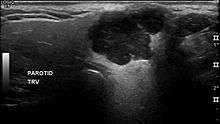

In terms of imaging studies, ultrasound can determine and characterize superficial parotid tumors. Certain types of salivary gland tumors have certain sonographic characteristics on ultrasound.[4] Ultrasound is also frequently used to guide FNA or core needle biopsy.

- ↑ Białek EJ, Jakubowski W, Karpińska G (Sep 2003). "Role of ultrasonography in diagnosis and differentiation of pleomorphic adenomas: work in progress". Arch Otolaryngol Head Neck Surg. 129 (9): 929–33. doi:10.1001/archotol.129.9.929. PMID 12975263.